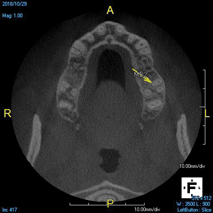

(6.) A lateral cyst associated with tooth No. 12 was asymptomatic and misdiagnosed on a periapical radiograph, but it was correctly diagnosed thanks to this CBCT slice of the maxilla that isolates the lesion.

Figure 6